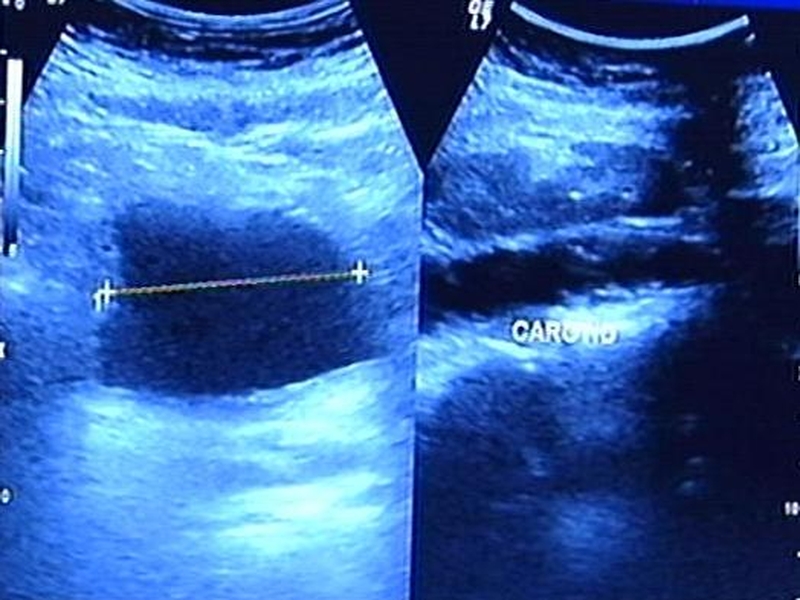

Image diagnostic - Improved tests for cancer

However, increased survival rates were due to improved testing and diagnosis, it said.